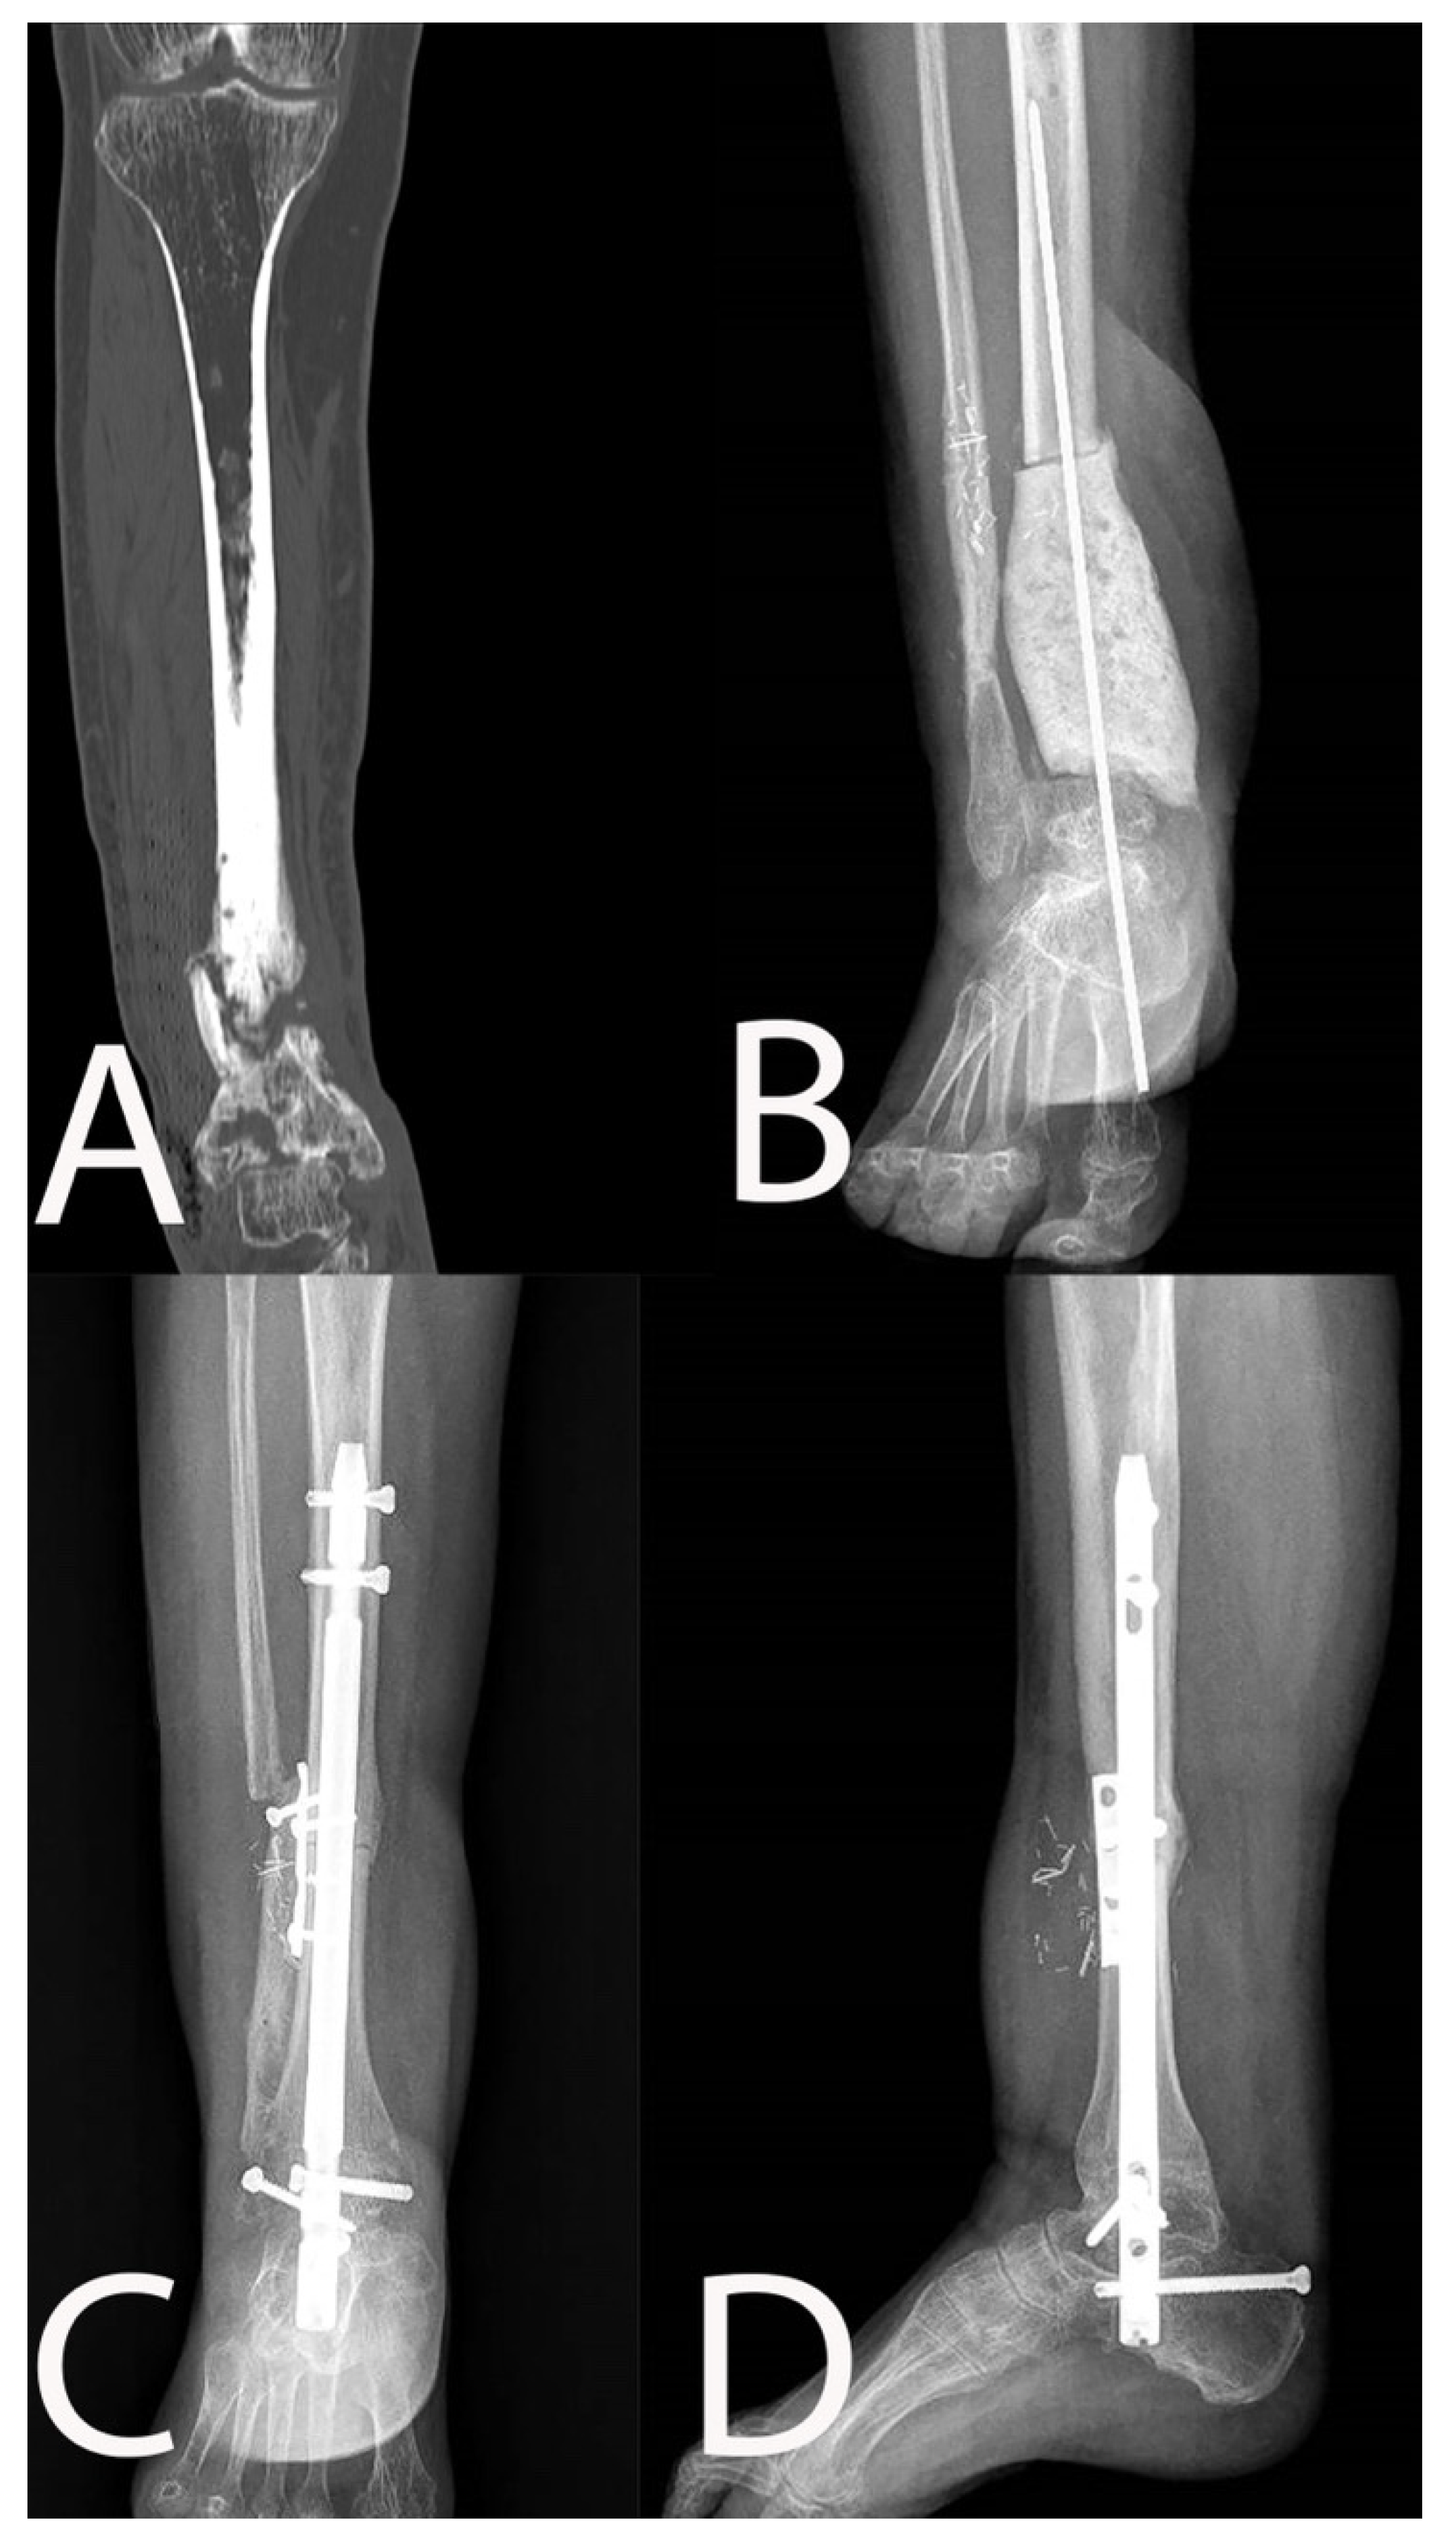

| 1 | 63, M | 2 | No | 4 | Yes | Type 4 | Type 4 Bl |

| 1 | Resection | Yes | 120 | MRSA + E. faecalis + P. stutzeri | ALT | 37 | No | ||

| 9 | Resection | Yes | 100 | MRSA + P. aeruginosa + E. faecalis | ALT | 30 | No | ||

| 10 | Resection | No | 100 | MSSA | ALT | 34 | No | ||